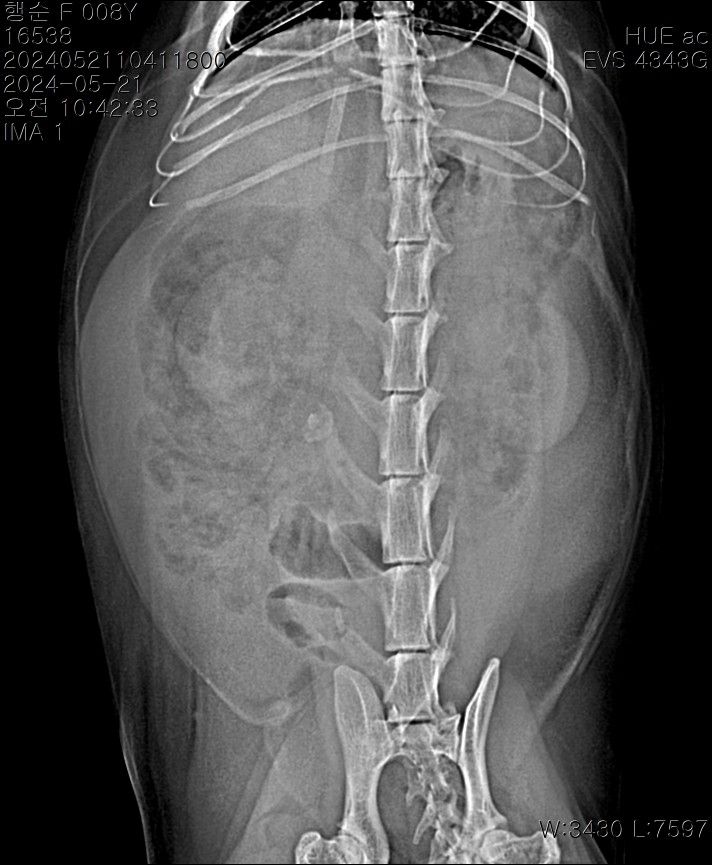

중등도 이상의 복수가 있는 상태이며 8세령이라면 복수의 원인으로 장파열에 의한 세균 감염성 복막염, 림프종과 같은 종양성 질환, 심장 질환, 대사성 질환, 고양이 전염성 복막염 등 다양한 원인을 고려해야 합니다. 복수에 대한 복수 검사를 기본으로 전신적인 종합검사가 필요합니다.